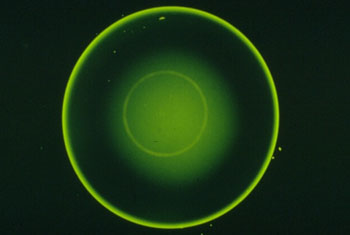

| Fluobild, Grad 0: |

| Die Rückfläche der Kontaktlinsen

läuft parallel zur Hornhautrückfläche. Zu Unterscheiden

sind hier zwei Fälle: |

Sphärische Hornhaut:

Keine oder nur minimale Differenz der zentralen Hornhautradien. Es

entsteht ein gleichmäßiges Auflage-bild. |

Torische Hornhaut:

Bei Radiendifferenzen wird die KL in der Regel parallel zum flachen

HH-Meridian angepasst. Es entsteht eine so genannte Breitbandauf-lage. |